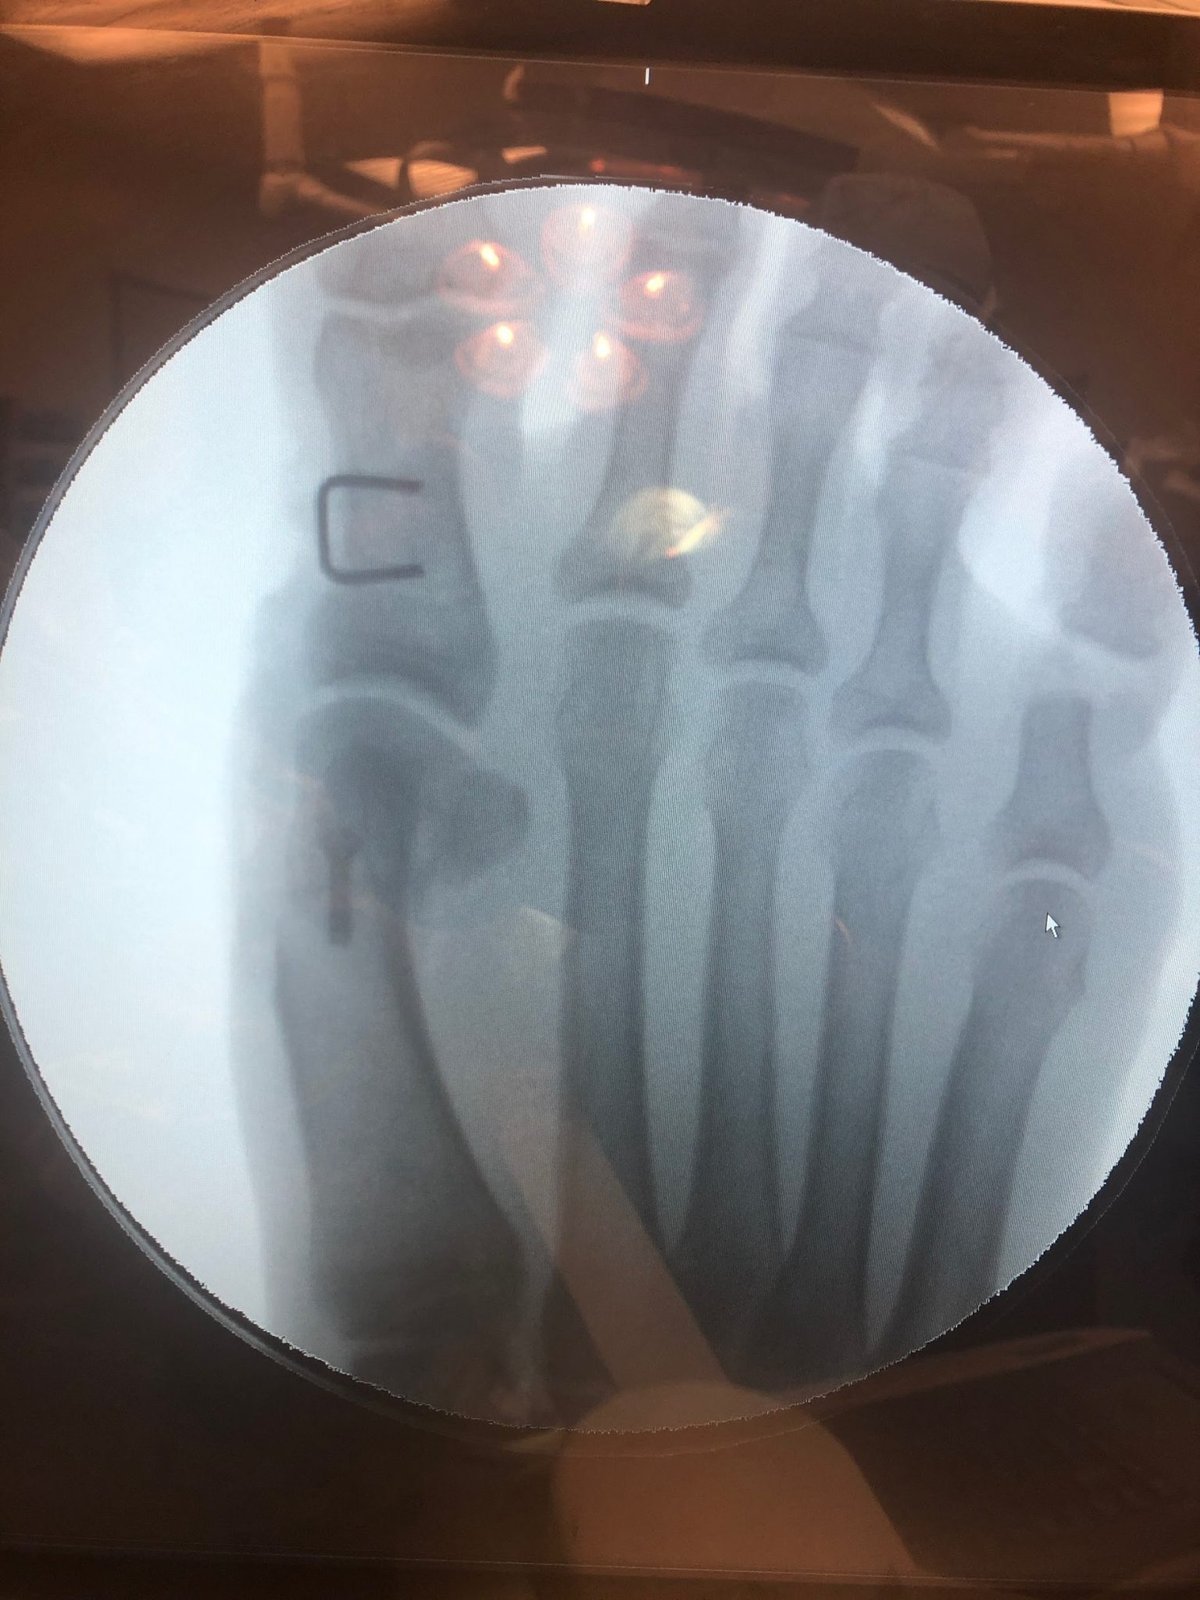

- Osteotomy: This involves cutting and realigning the bone in your big toe to correct the deformity. It's one of the most frequently performed bunion surgeries.